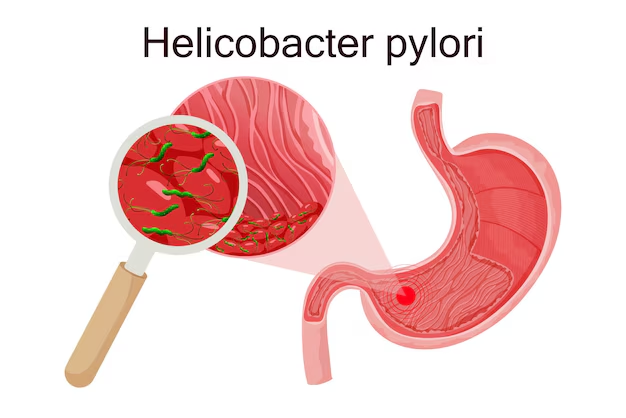

العدوى الفيروسية المزمنة (التهاب الكبد B وC): تُعد من أبرز الأسباب وأكثرها شيوعًا، حيث يؤدي استمرار العدوى الفيروسية لفترات طويلة إلى التهاب مزمن في أنسجة الكبد يسبب تدهورًا تدريجيًا في وظائفه.

العدوى البكتيرية وبعض الأمراض المزمنة: مثل داء الزهري والبروسيلا، والتي قد تؤدي في بعض الحالات إلى التهاب كبدي مزمن.

هل تليف الكبد معدي؟

تعتمد قابلية العدوى على السبب المؤدي لتليف الكبد؛ فإذا كان ناتجًا عن عوامل غير معدية مثل الكحول أو الدهون، فلا ينتقل للآخرين. أما إذا كان مرتبطًا بعدوى فيروسية مثل التهاب الكبد B أو C، فقد تكون العدوى الفيروسية نفسها مُعدية وليست حالة التليف بحد ذاتها.